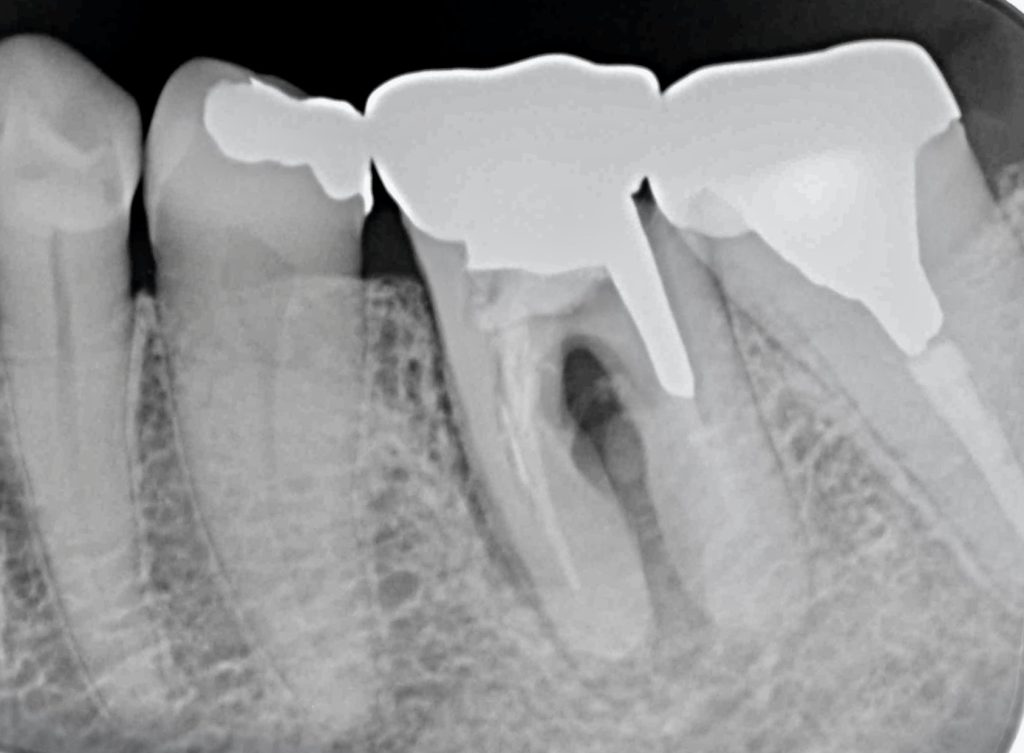

下記のケースは4年前から抜歯が必要ですとご指摘しておりました。

遠方より久しぶりの来院で痛みがが出てきたそうです。

歯根破折を起こし、周囲の骨が炎症を起こしていました。

骨の再生のみならず、歯肉も不足していた為、歯肉移植を行いメンテナンスしやすい環境を整えました。

これにより長く機能させる事が可能となったと思います。

下記の症例にかかる費用    約72万円(税抜)